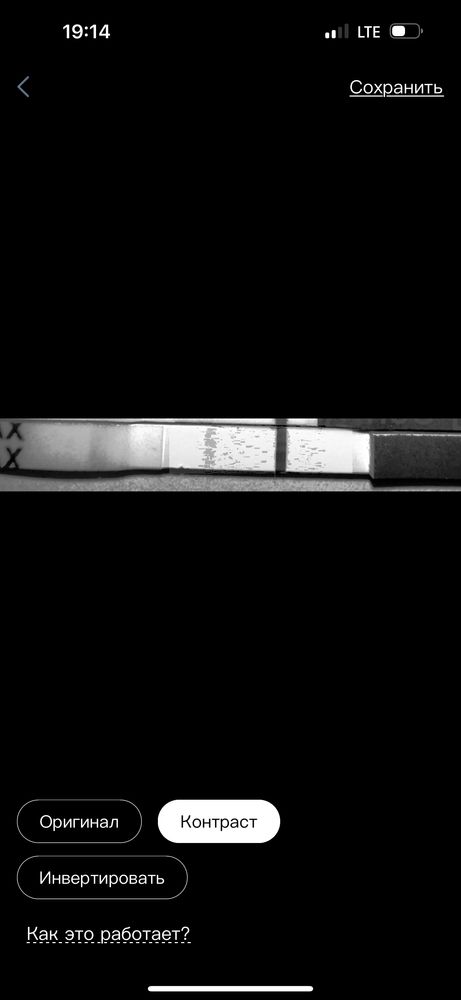

я вижу здесь розовенькие полосочки но честно им не верю что вы скажете? Последний тест прогнала через прогу полоска вроде мне не мерещиться не знаю даже

Укол уже вышел так как один тестам вроде как вообще чистый мне вот интересно реагент это или что склоняюсь больше к реагенту